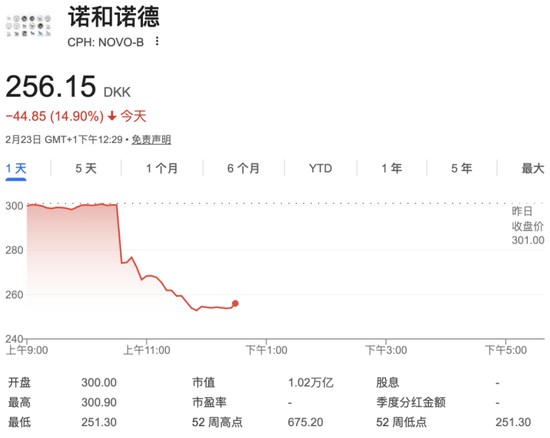

今日,在欧洲交易时段,减肥药巨头诺和诺德股价大幅跳水,一度暴跌超15%,在美股盘前交易中,诺和诺德股价亦暴跌超14%。消息面上,该公司的下一代减肥药物CagriSema的实验效果不及美国礼来公司的Zepbound。

2月23日,欧洲股市开盘后,诺和诺德股价直线跳水,盘中一度大跌超15%,截至北京时间19:30,跌幅仍达14.9%,跌至2021年6月以来最低水平。美股盘前,诺和诺德股价亦大跌超14%。

今年以来,诺和诺德爆雷不断。2月初,该公司发布的2026年业绩指引大幅低于市场预期,预计全年销售额按固定汇率计将下降5%至13%,远超分析师预期的约1.4%降幅。受此影响,其美股股价单日暴跌超14%。